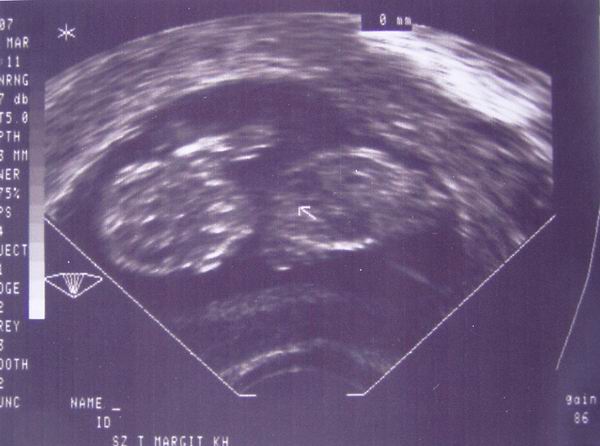

ismet a nagy elveszettsegbol jelentkezek be, mert nem szamoltam be a tegnap elotti uh-rol: a babam rendben van, pulzalt a kis szive, mar a crl 22mm (huuu!!!) es voltak neki vegtagkezdemenyei is, szoval fantasztikus kolyok.

nehany nappal kisebb a mensi szerinti koranal, de ez termeszetes, mert nekem nem 28 napos a ciklusom, hanem 32-33. A mehszajam is rendben van, pedig en eskudni mertem volna ra, hogy nyilik, allandoan ezt erzem utro dugdosasnal, dehat a doki biztosan jobban ert hozza...